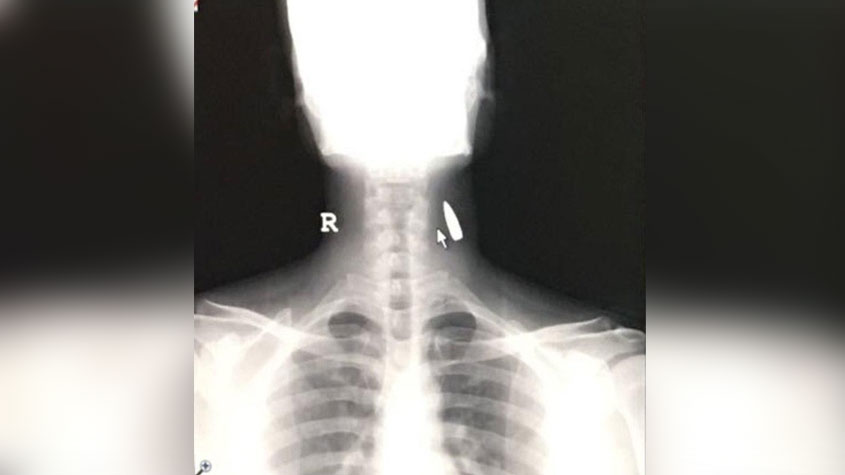

وأشارت المصادر إلى أن الوافد الهندي نقل إلى المشفى بعد إصابته على الفور، وأظهرت الأشعة وجود الرصاصة في رقبته، وعمل الأطباء على استخراجها والاطمئنان على وضعه الصحي.

وأوضحت أن الوافد الهندي كان يعمل بمغسل سيارات في المعارض بالحوية شمال الطائف، قبل أن يفاجئ برصاصة مجهولة تخترق السقف الحديدي وتُصيبه في جزء جانبي من عنقه واستقرت بداخله.